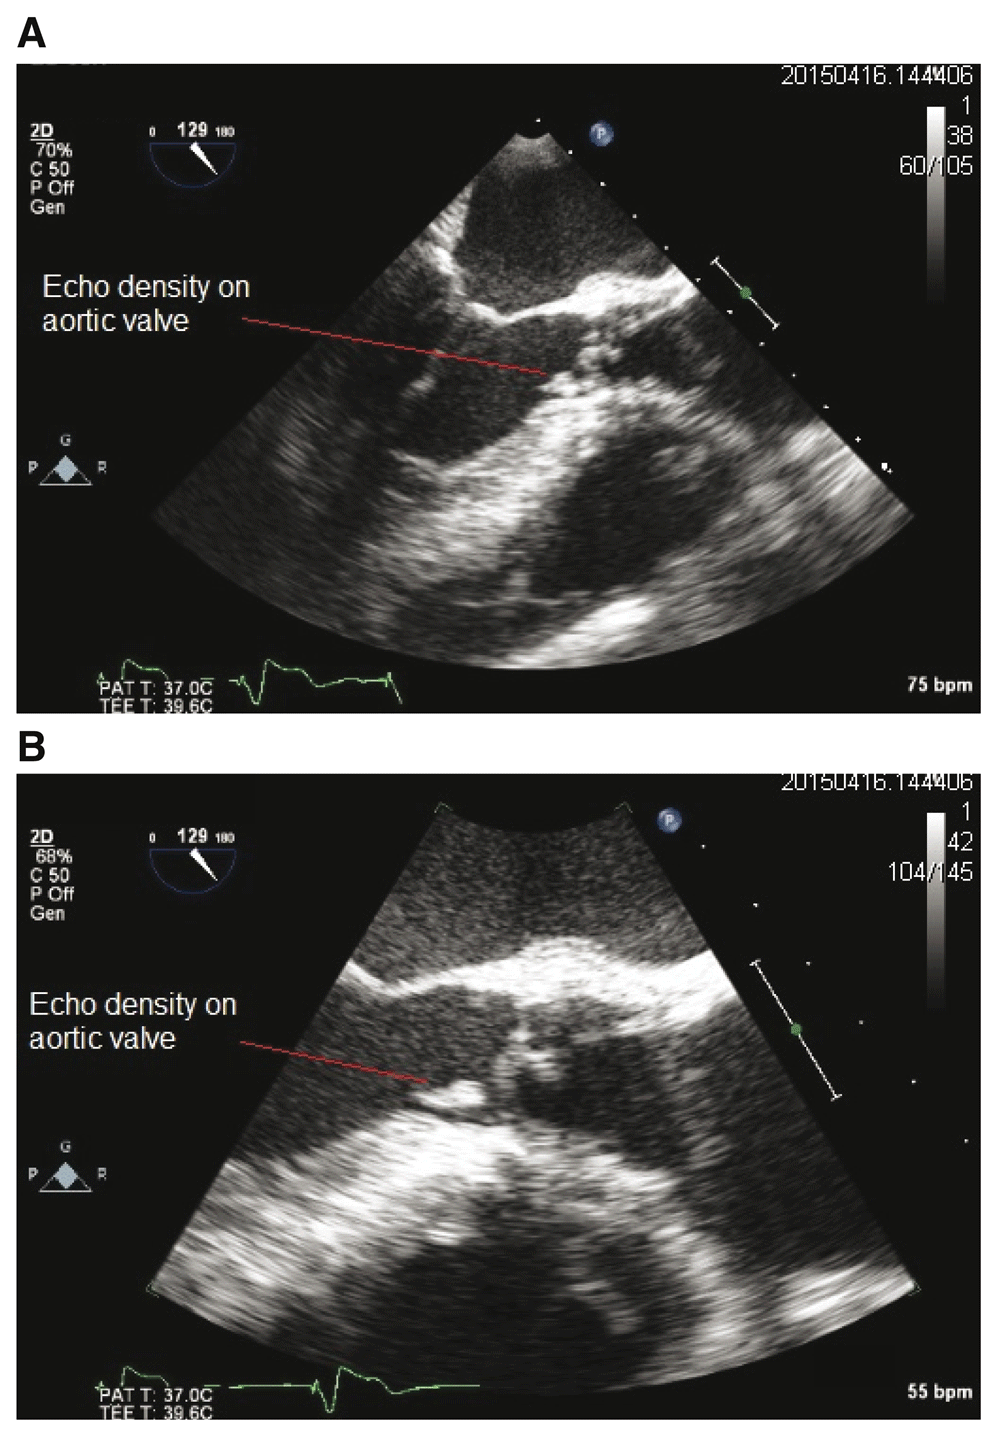

A trans-thoracic echocardiogram showed mild aortic regurgitation and mitral regurgitation with no clear vegetation, however, trans-esophageal echocardiogram (TOE) showed a moderate aortic regurgitation due to a large mobile vegetation on the bio-prosthetic aortic valve with normal left ventricular function, no peri-valvular abscess was noted (See Image 1a and 1b).

1A: Transesophageal echocardiogram (TEE), mid-esophageal view showing mobile echo density on prosthetic aortic valve. 1B: Transesophageal echocardiogram (TEE), mid-esophageal view enlarged to show mobile echo density on prosthetic aortic valve.